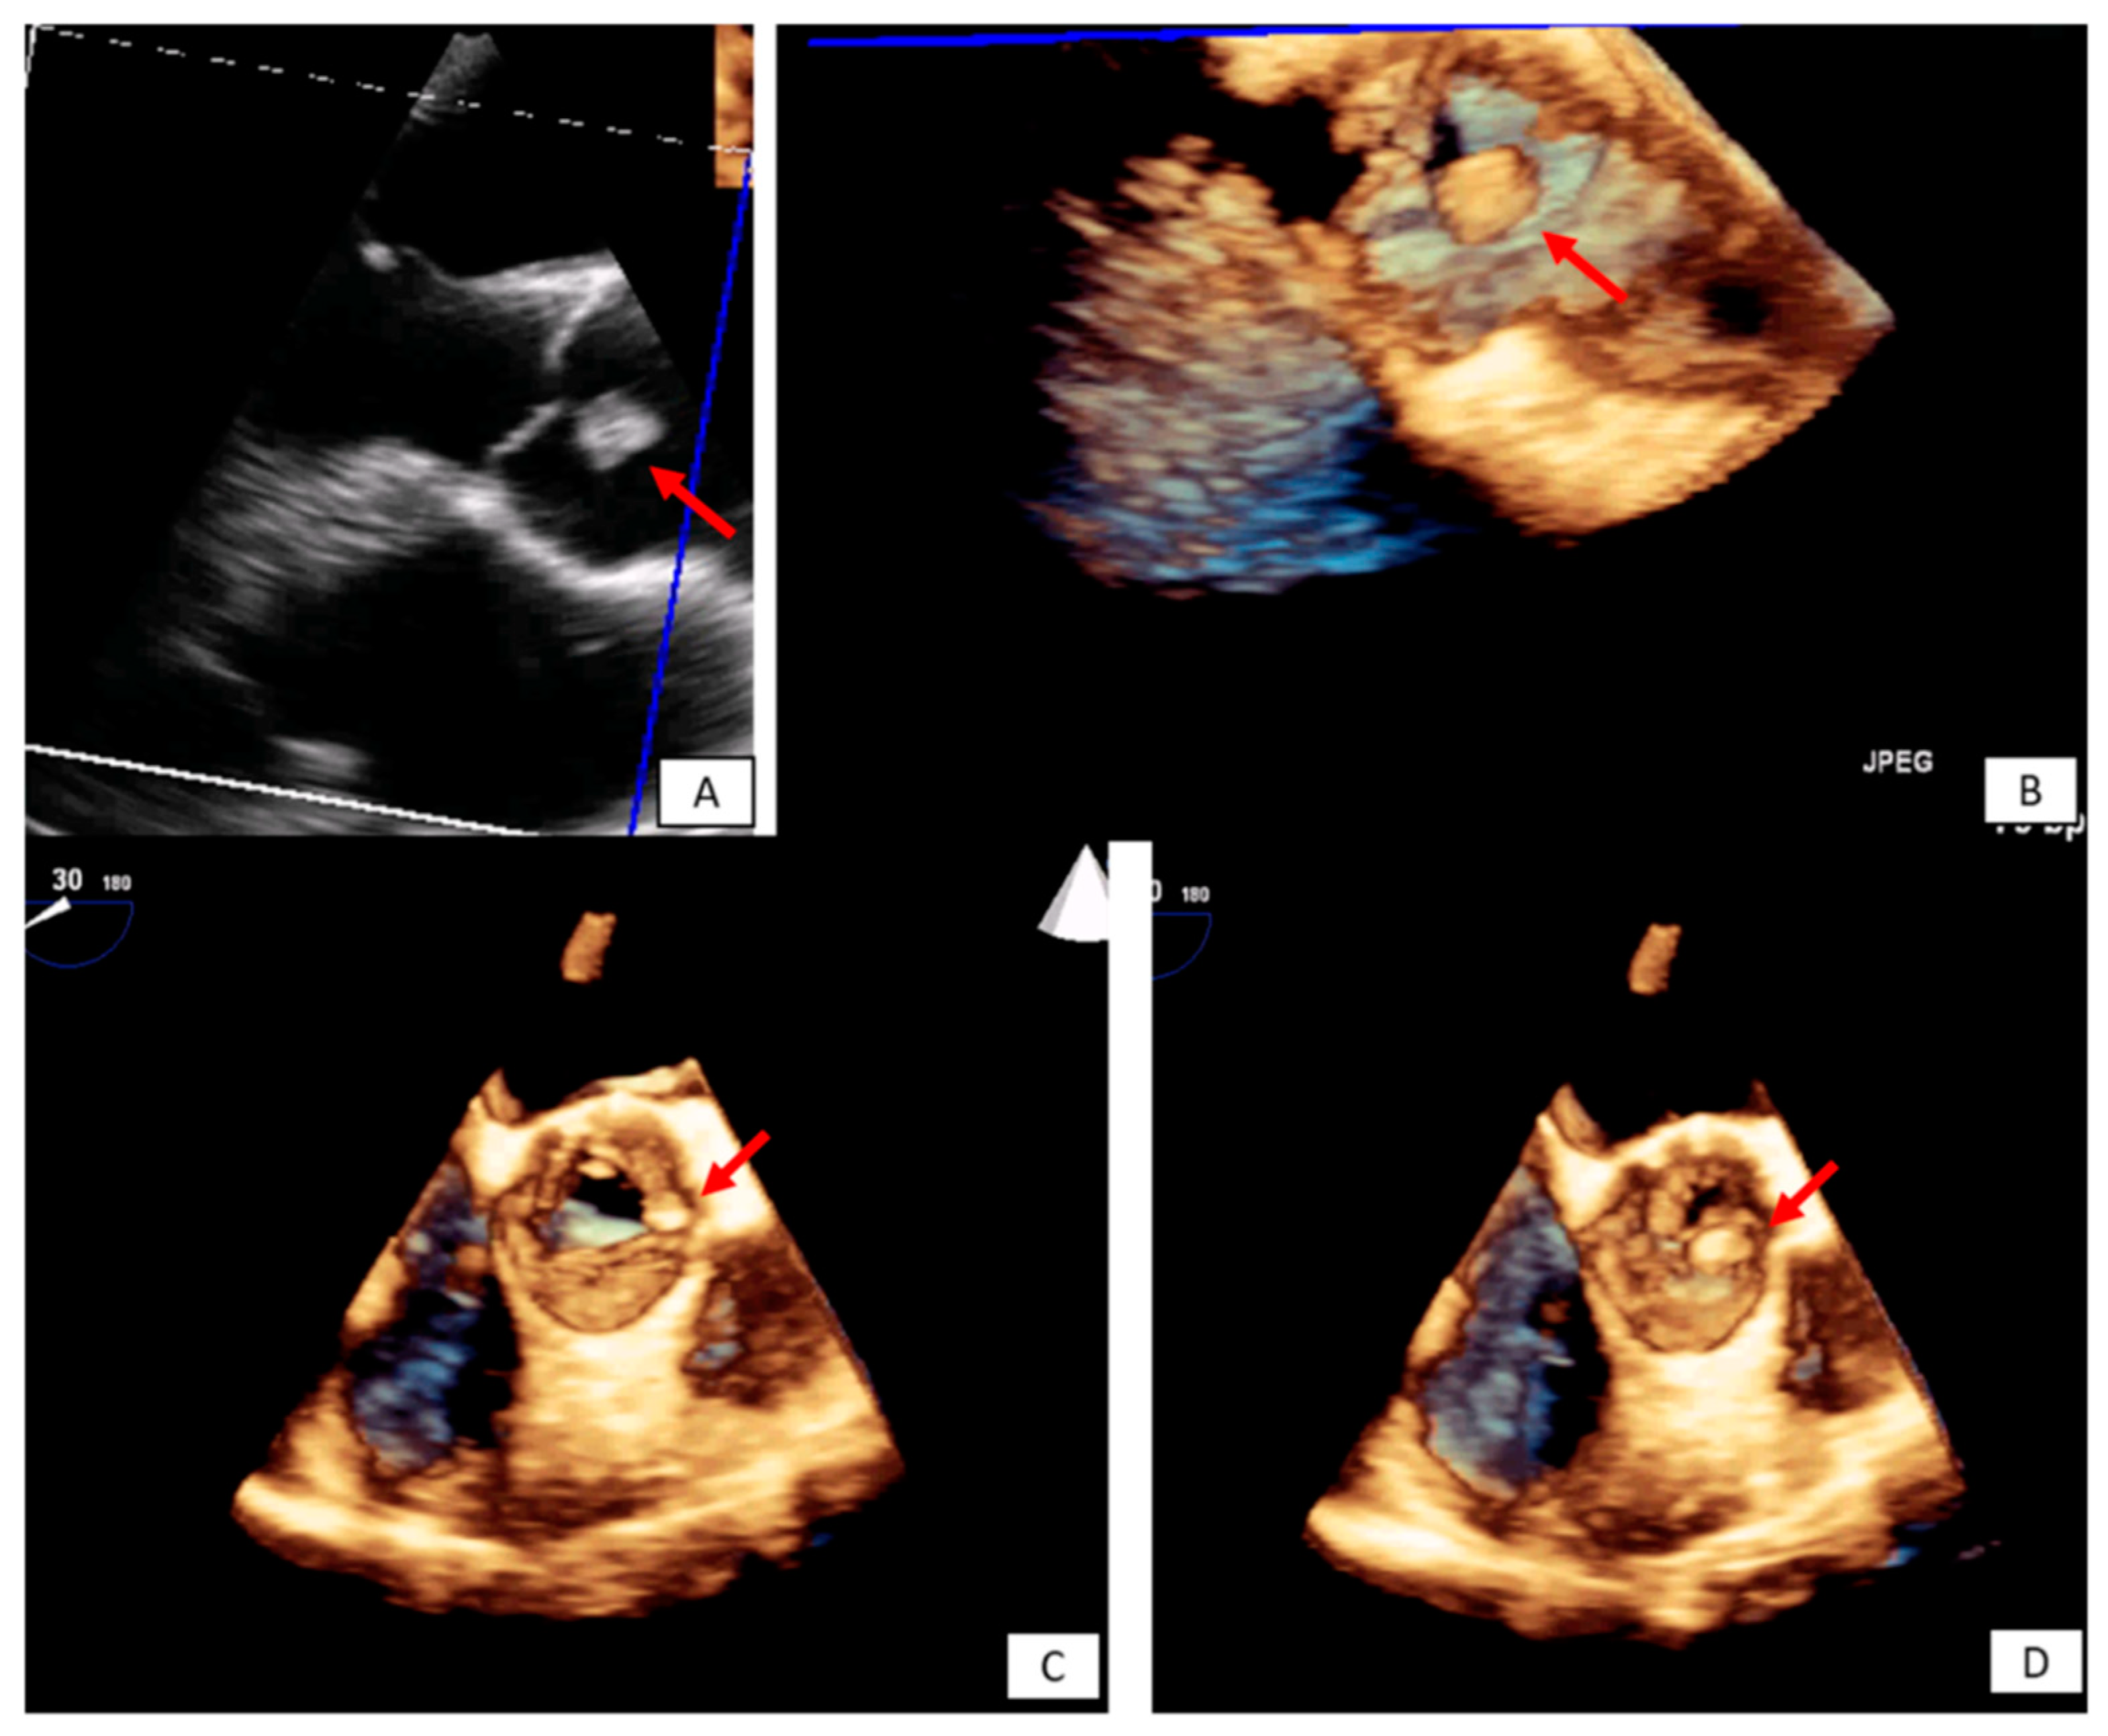

3.2. Transesophageal Echocardiography

- Zaragosa-Macias, E.; Chen, M.A.; Gill, E.A. Real time three-dimensional echocardiography evaluation of intracardiac masses. Echocardiography 2012, 29, 207–219. [Google Scholar] [CrossRef] [PubMed]

- Aggeli, C.; Poulidakis, E.; Felekos, I.; Aggeli, A.; Stefanadis, C. An octopus-like myxoma depicted by real-time 3D transesophageal echocardiography. Hell. J. Cardiol. 2012, 53, 470–471. [Google Scholar]